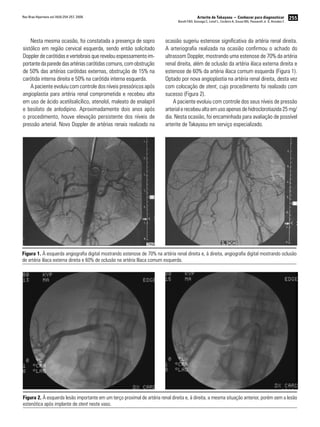

A arteriografia realizada na ocasião confirmou o achado do

ultrassom Doppler, mostrando uma estenose de 70% da artéria

renal direita, além de oclusão da artéria ilíaca externa direita e

estenose de 60% da artéria ilíaca comum esquerda (Figura 1).

Optado por nova angioplastia na artéria renal direita, desta vez

com colocação de stent, cujo procedimento foi realizado com

sucesso (Figura 2).

Figura 1. À esquerda angiografia digital mostrando estenose de 70% na artéria renal direita e, à direita, angiografia digital mostrando oclusão

de artéria ilíaca externa direita e 60% de oclusão na artéria Ilíaca comum esquerda.

Figura 2. À esquerda lesão importante em um terço proximal de artéria renal direita e, à direita, a mesma situação anterior, porém sem a lesão

estenótica após implante de stent neste vaso.